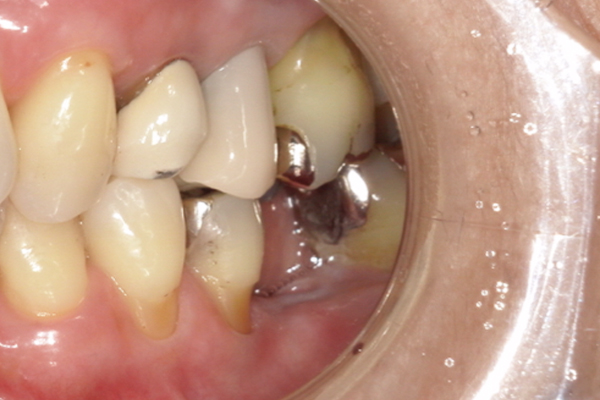

| 主訴 | 奥歯で噛めない、顎が痛い |

|---|---|

| 治療内容 | 奥歯のインプラント治療、前歯・奥歯の被せ物治療 |

| 治療期間 | 6ヶ月 |

| 治療費 | 350万円 |

| 治療リスク | 被せ物をつけた初期の段階で歯がしみることがある(時間とともに改善する) インプラント治療後に3日程度痛みと腫れを伴うことがある |